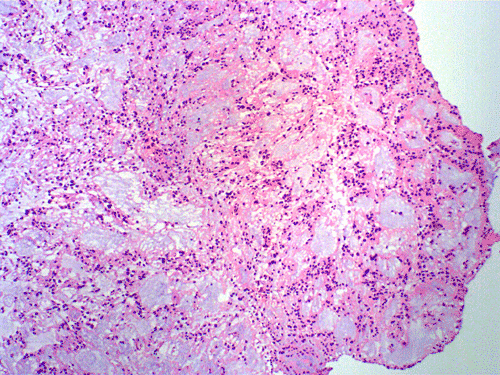

On cytologic preparations, there are clumps of tissue that do not smear out well (Panel A). On higher magnification, these tissue clusters are composed of large blobs of bluish, acellular, mucoid material admixed with cells with relatively uniform, bland nuclei and small amount of cytoplasm (Panel B). In the less tightly packed areas, the long cytoplasmic processes of the cells can be well appreciated (Panel C). These long processes are highly suggestive of a glial neoplasm. On frozen sections, the lesion is composed of multiple blobs of bluish, mucoid material surrounded by tumor cells (Panel D and E). Features of the paraffin sections are not that much different from that of the frozen sections (Panel F G H).

Histopathology: The salient feature of myxopapillary ependymomas is a rich, thin walled micropapillary bundle surrounded by a single of epithelium that varies from low cuboidal to columnar. The cells typically have rounded nuclei with a delicate, rather open chromatin and a moderate amount of amphophilic cytoplasm. The cores of the papillae consist of blood vessels surrounded by a variable amount of mucinous matrix. The amount varies from small to substantial. The vessels are characterized by extensive thickening and hyalinization of the vessel wall. Ins some tumors, there are components with features of conventional ependymomas 24. Mitotic activity is very low or absent 25. Myxopapillary ependymomas usually have sharply defined margins, although nerve roots may be enclosed. A proportion of tumors are surrounded by a condensed connective tissue capsule 11.